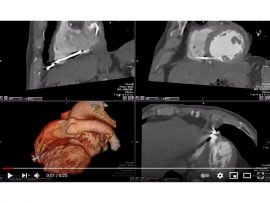

Read MoreVVI PACEMAKER WIRE RV PERFORATION Mohamed Gibreel , FEBR (Fellowship of Egyptian Board of Radiology ) Cardiac imaging consultant at Aswan heart center -Magdi Yacoub Foundation , Egypt..